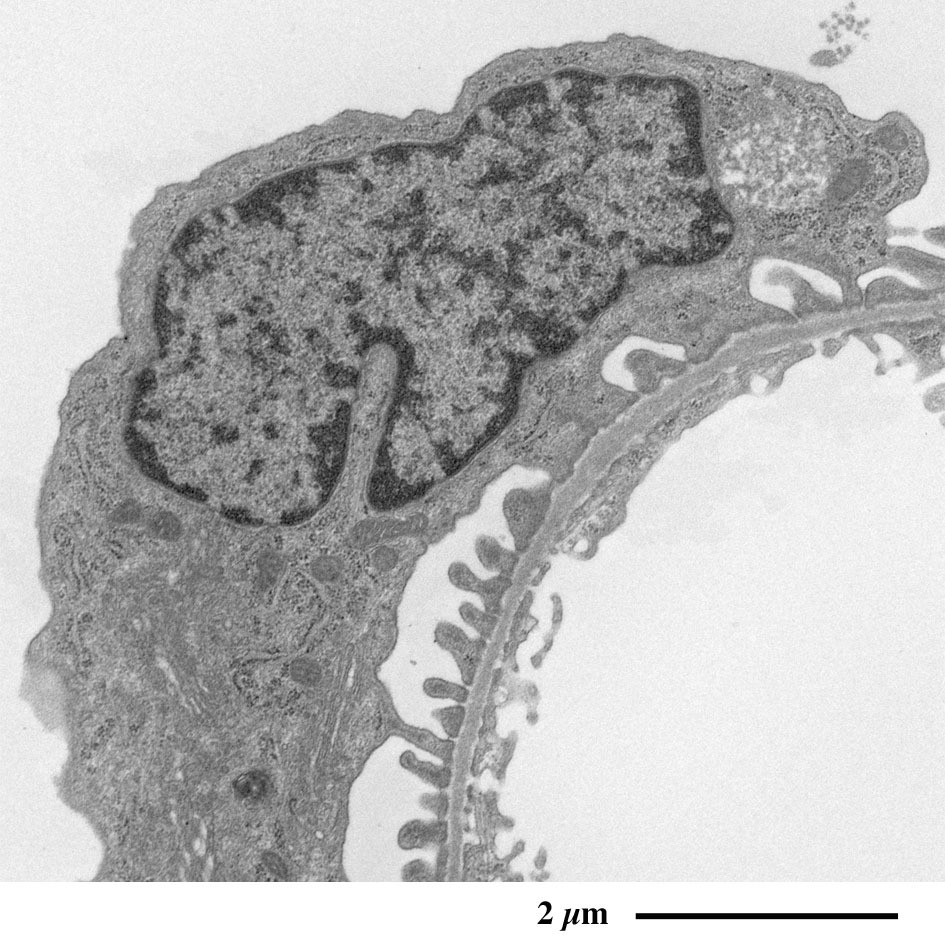

【 超薄切片の透過型電子顕微鏡画像 】

Transmission electron microscopic image of ultrathin section

糸球体の電子顕微鏡像

足細胞を含むボウマン腔を縫うように毛細血管が走行し、

外周をボウマン囊が取り囲みます。